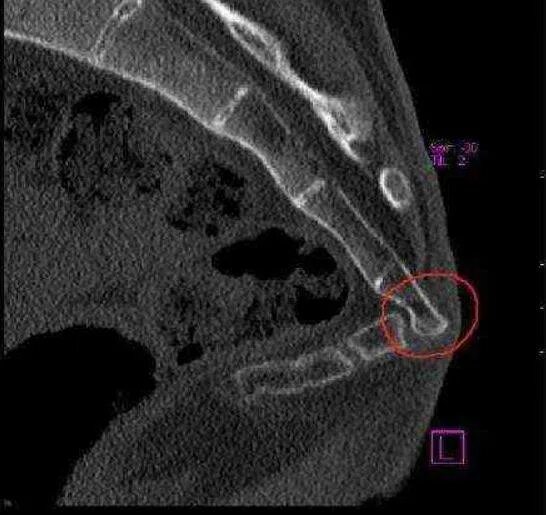

Снимок копчика